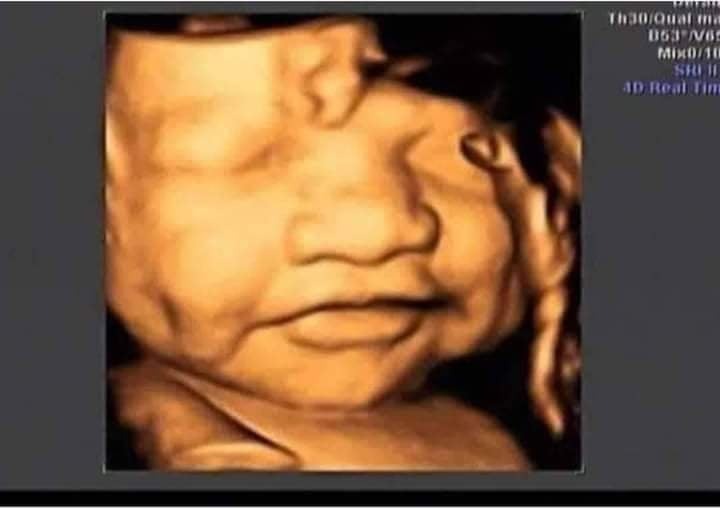

Có ai xin vía má lúm k ạ 😂😂😂

E dc 34w rồi hqua đi siêu âm bsi bảo to quá mẹ hãm ăn lại k ăn dao 😥😥. Đc 2kg6 rồi